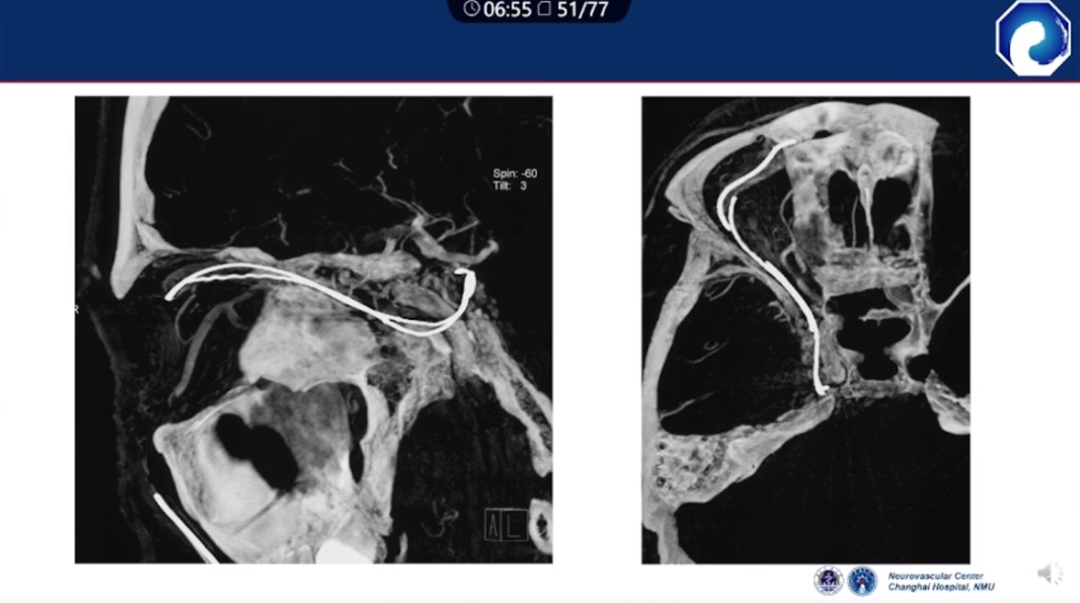

靶向性栓塞可以减少海绵窦分隔的过渡栓塞,有利于减少颅神经并发症,恢复海绵窦的正常引流功能。